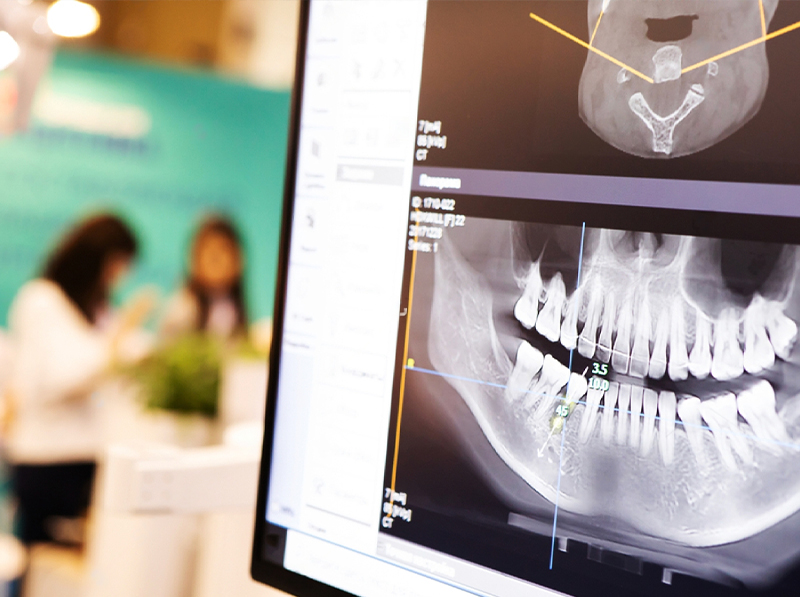

With the advent of cone beam CT scan technologies (CBCT), some offices performing dental implant surgeries have also invested in CT imaging machines that help facilitate the most accurate placement of any implant. A CBCT is an X-ray machine that takes a 3-dimensional image of the head rather than just a 2-dimensional picture like a conventional dental x-ray or panoramic film. A cone beam 3D x-ray is a digital imaging system that relies on computer processing and special image manipulation software to digitally reconstruct the entire bony structure of a person’s skull. If an implant surgeon like Dr. Haywood has precise information about where bone is or where it needs to be repaired, he can offer patients insight into their needs based on the most current diagnostic technology available.